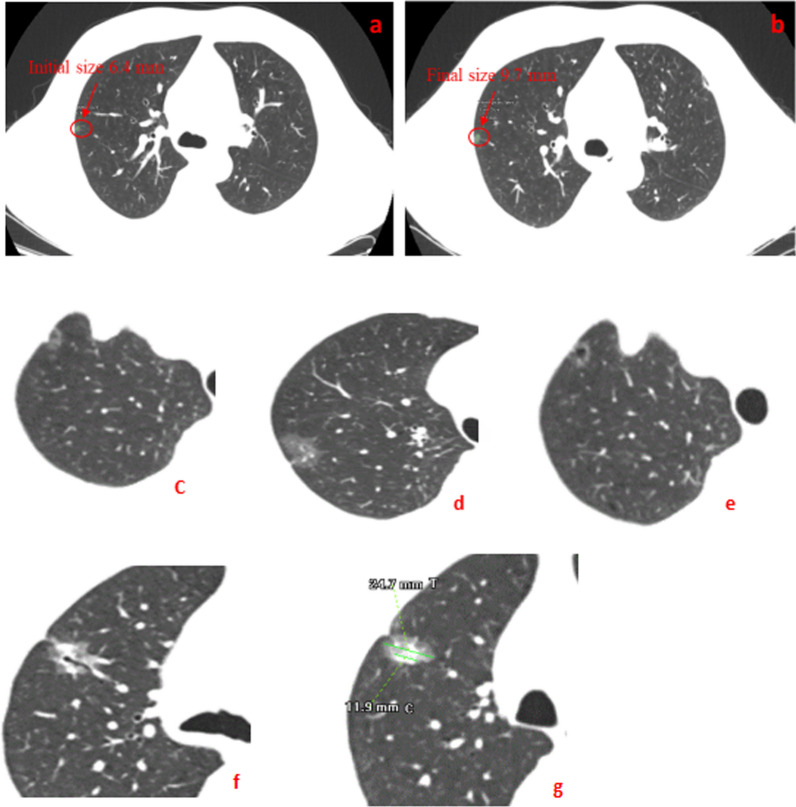

Two board-certified pathologists with 10-year experience of in pathological diagnosis of lung cancer) reviewed the CT images with GGN. They carefully checked the radiology features of both lungs (window width of 1500 HU and window level of 600 HU). The mediastinal windows (width of 500 HU and level of 50 HU) were set as following as in Fig. 1a,b diameter of GGNs (maximal diameter on the axial section) (c) Pleural indentation sign (linear attenuation toward the pleura from GGNs),(d) Lobulation sign, i.e., the appearance of a wavy or scalloped configuration in the lesion’s surface, (e) vacuole sign (single or multiple cystic cavities with a diameter of less than 5 mm in GGNs) (f) Spiculation sign (the presence of strands from the nodule margin into the lung parenchyma, but not reaching the pleural surface); Air bronchus sign (air-filled bronchi in the GGNs); Vascular convergence sign (GGNs with dilated, convergent or tortuous supplying vessels); (g)The maximal diameters of consolidation in tumors (C) and of the whole tumor including GGO (T) in lung window. GGNs were categorized into 2 groups by CTR (C/T ratio) of 0.5; tumor blood vessel diameter (the supplying microvascular with the nodule diameter of larger than 0.5 mm penetrating the nodules. The diameter here was the sum while multiple vessels were observed If there were two vessels, the diameter was the sum of two) as shown in Fig. 2. We measured the value of the vessel and magnified the CT picture by almost 500% which made its precision approach 0.1 mm. The other author rechecked the image interpretation before reaching a consensus. The clinical features of the patients included age, sex, smoking history, family history of tumor, postoperative pathology, degree of infiltration and size of pulmonary nodules. Pathological diagnoses of GGNs after surgically resection were also recorded and classified according to 2015 WHO Classification criteria for lung adenocarcinoma [19].

Fig. 1.

The size change of a GGO from the initial (a) to the final period of 3-year (b) during this study. (c) Pleural indentation sign (d) Lobulation sign (e) vacuole sign (f) A CT imaging included spiculation sign, air bronchus sign and vascular convergence sign, (g) The maximum diameter of consolidation in tumor (C) and the greatest diameter of the whole tumor including GGO (T)